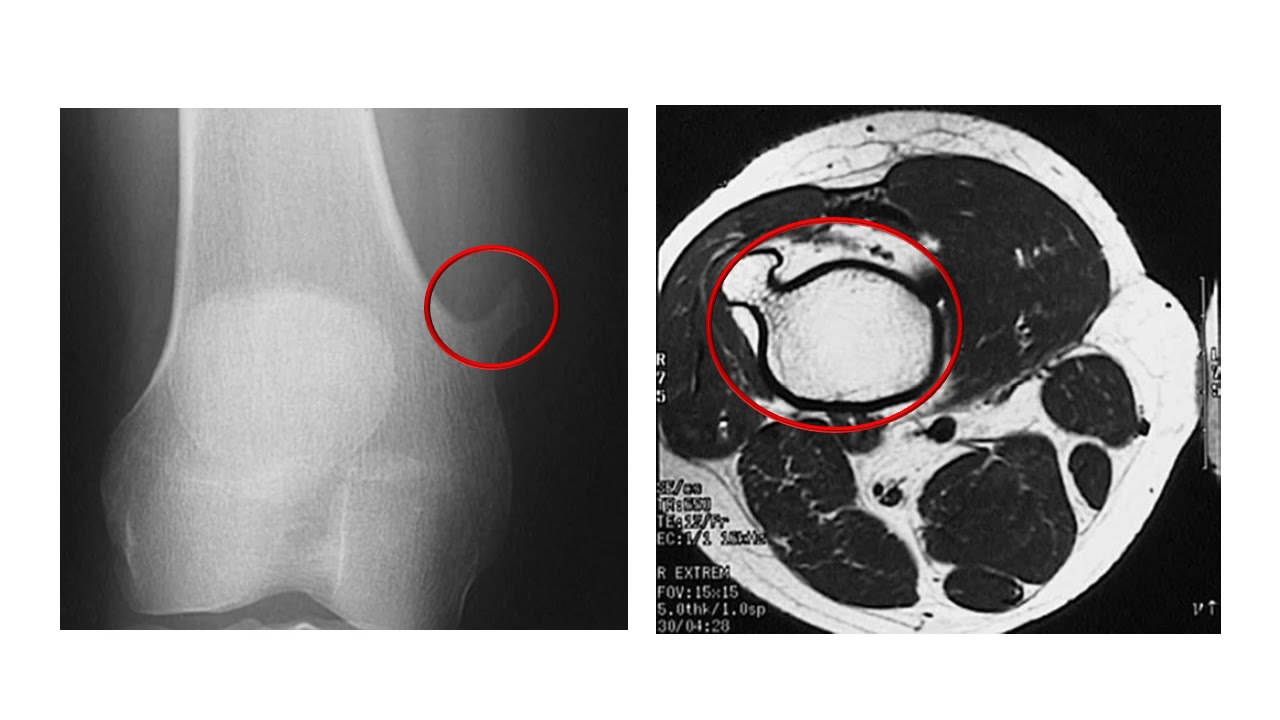

Опухоль без кровотока

Опухоль без кровотока 110 фотографий